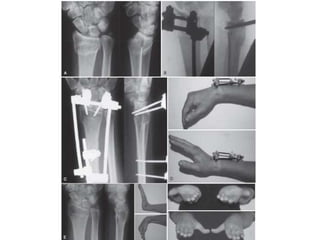

Tutores externos

• Fragmentos son pequeños y cercanos a la articulación,

• Gran conminución

• Fractura expuesta

• Se puede utilizar clavos percutáneos y emplearlos por un lapso de 4 a

6 semanas

TECNICA DE TUTOR MAS AUMENTO CON

CLAVOS

Distal Radius Fractures: Approaches, Indications, and Techniques. Current concept. Ram K. Alluri. 2016 by the American Society for Surgery of the Hand.

AO Surgery

Fijación externa combinada con percutanea

Reducción fijación externa combinada con

reducción abierta ,síntesis con agujas de Kirschner